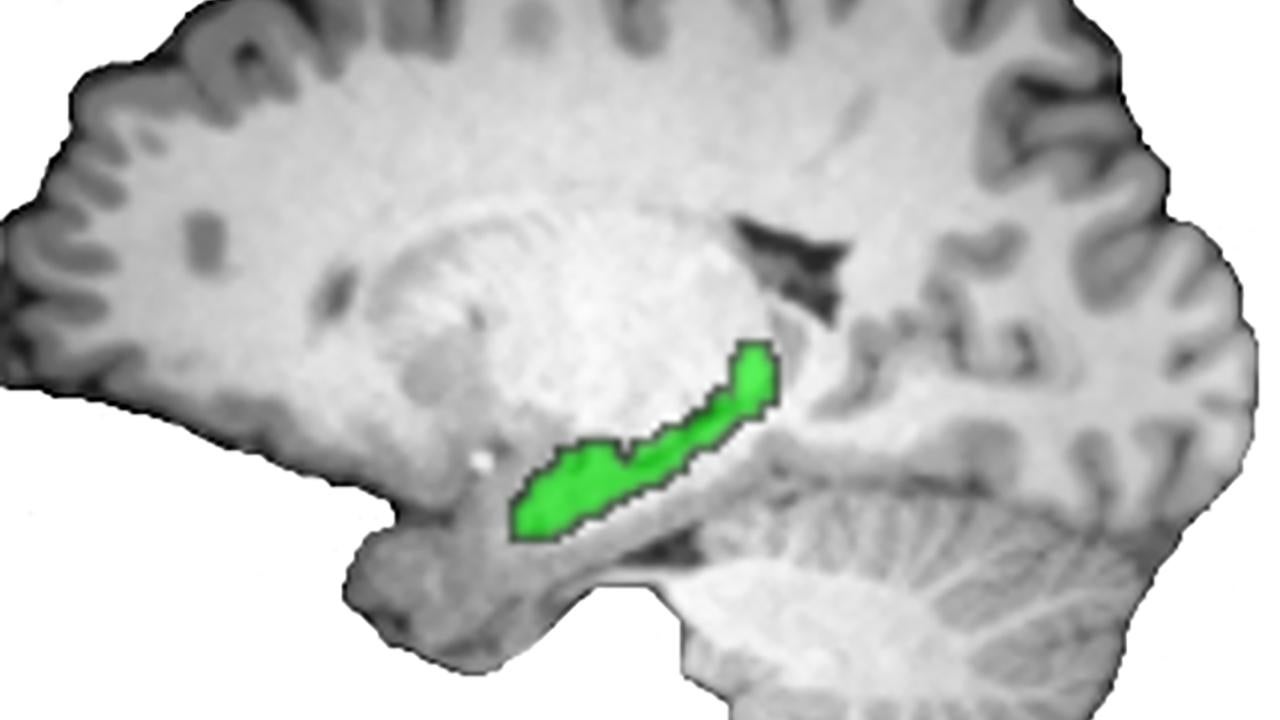

MRI image of brain with hippocampus in green

A new brain imaging study shows that the hippocampus (green) is the brain's master storyteller, weaving memories of past events into a coherent narrative. Image: Brendan Cohn-Sheehy, Center for Neuroscience

People love stories. We find it easier to remember events when they are part of an overarching narrative. But in real life, the chapters of a story don’t follow smoothly one from another. Other things happen in between. A new brain imaging study from the Center for Neuroscience at the University of California, Davis, shows that the hippocampus is the brain’s storyteller, connecting separate, distant events into a single narrative. The work is published Sept. 29 in Current Biology.